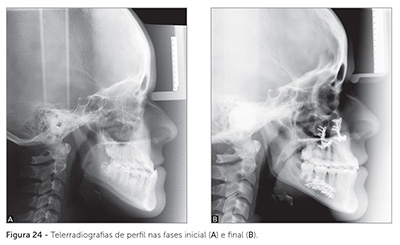

A idade mínima para indicação de cirurgia ortognática em fase de crescimento estará diretamente relacionada ao grau de desenvolvimento da dentição. Portanto, em todos os tipos de deformidades faciais severas em que a abordagem da cirurgia precoce for considerada — seja na hiperplasia ou hipoplasia mandibular, na hipoplasia maxilar ou na hiperplasia maxilar vertical —, o estágio do desenvolvimento dentário será determinante para o procedimento cirúrgico. O grau de desenvolvimento dos caninos superiores é importante para avaliarmos a viabilidade da cirurgia maxilar sem dano à estrutura dentária. É recomendável fazer a cirurgia de avanço mandibular após a erupção dos segundos molares inferiores; o ideal seria ter todos os dentes permanentes já irrompidos, exceto os terceiros molares. Algumas vezes, temos que esperar um pouco para realizar a cirurgia, para que ocorra maior desenvolvimento dentário. Um exemplo de paciente tratado aos 12 anos de idade pode ser visto nas Figuras 21 a 25, quando o desenvolvimento dentário já permitia as manobras cirúrgicas necessárias. O que não pode acontecer, seja por essa ou por outra razão, é propormos a cirurgia a um paciente Classe III em seus 15 ou 16 anos de idade. Essa não me parece uma abordagem sensata. Seria correto aguardar até os 18 anos de idade e realizar o consagrado tratamento ortodôntico-cirúrgico da Classe III.